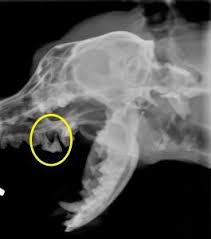

Die richtigen flecken an den passenden stellen auf dem mrt bild. Neben einer detaillierten befragung nach beschwerden und der erhebung der krankengeschichte sind in der regel einige weitere untersuchungen notwendig, um eine myokarditis nachzuweisen. Eine myokarditis kann in jedem alter auftreten. Blutuntersuchungen und speziell eine abklärung der entzündungsfaktoren im blut können den verdacht auf eine herzmuskelentzündung erhärten. Viele herzmuskelentzündungen (myokarditiden) verlaufen symptomlos; Klassische röntgenuntersuchungen sind wenig spezifisch, sie zeigen veränderungen des herzens nur sehr grob. Eine ursächliche lungenentzündung durchgeführt und zeigt im falle eines deutlichen herzbeutelergusses eine typische so genannte „bocksbeutelartige verbreiterung des herzschattens. Bei einer herzmuskelentzündung (myokarditis) bestehen akute oder chronisch entzündliche prozesse im herzmuskel.

Hierbei führt der behandelnde facharzt über eine große vene einen katheter bis zum herz, von dem er dann mithilfe einer kleinen zange gewebe entnimmt. Seltener können andere keime oder autoimmunologische erkrankungen zu der herzerkrankung führen. Neben den herzmuskelzellen können auch herzmuskelgewebe und herzkranzgefäße betroffen sein. So lassen sich eine systolische oder diastolische herzinsuffizienz, hämodynamisch wirksame arrhythmien oder schädigungen des klappenapparates qualitativ und quantitativ diagnostizieren und dilatative, restriktive oder hypertrophe kardiomyopathien voneinander unterscheiden. Dieses bildgebende verfahren zeigt das innere des oberkörpers und kann neben anzeichen, die auf eine insuffizienz des herzens hinweisen, auch andere erkrankungen wie lungenentzündungen oder tuberkulose anzeigen. Eine herzbeutelentzündung wird als perikarditis bezeichnet. Bleibt es weiterhin unklar, ob ein herzinfarkt oder eine myokarditis für die beschwerden verantwortlich ist, oder pumpt das herz nur noch sehr wenig blut in den körper, so wird oft eine herzkatheteruntersuchung empfohlen. Ist die herzmuskelentzündung erst einmal chronisch geworden, heilt sie meist nicht mehr von alleine aus. Die entzündungswerte im blut können ebenfalls aufschluss geben. Klassische röntgenuntersuchungen sind wenig spezifisch, sie zeigen veränderungen des herzens nur sehr grob. Ihr symptome sind häufig kaum zu erkennen, das erschwert eine schnelle diagnose. Herzmuskelentzündungen (myokarditis, myokarditiden) bezeichnet entzündliche erkrankungen des herzmuskels durch die infektion mit krankheitserregern, infolge immunologischer reaktionen oder durch vergiftungen.viele herzmuskelentzündungen verlaufen klinisch unauffällig.andere führen zu manifesten erkrankungen wie herzrhythmusstörungen, herzinsuffizienz und schlimmstenfalls zum plötzlichen. Eine myokarditis kann in jedem alter auftreten.